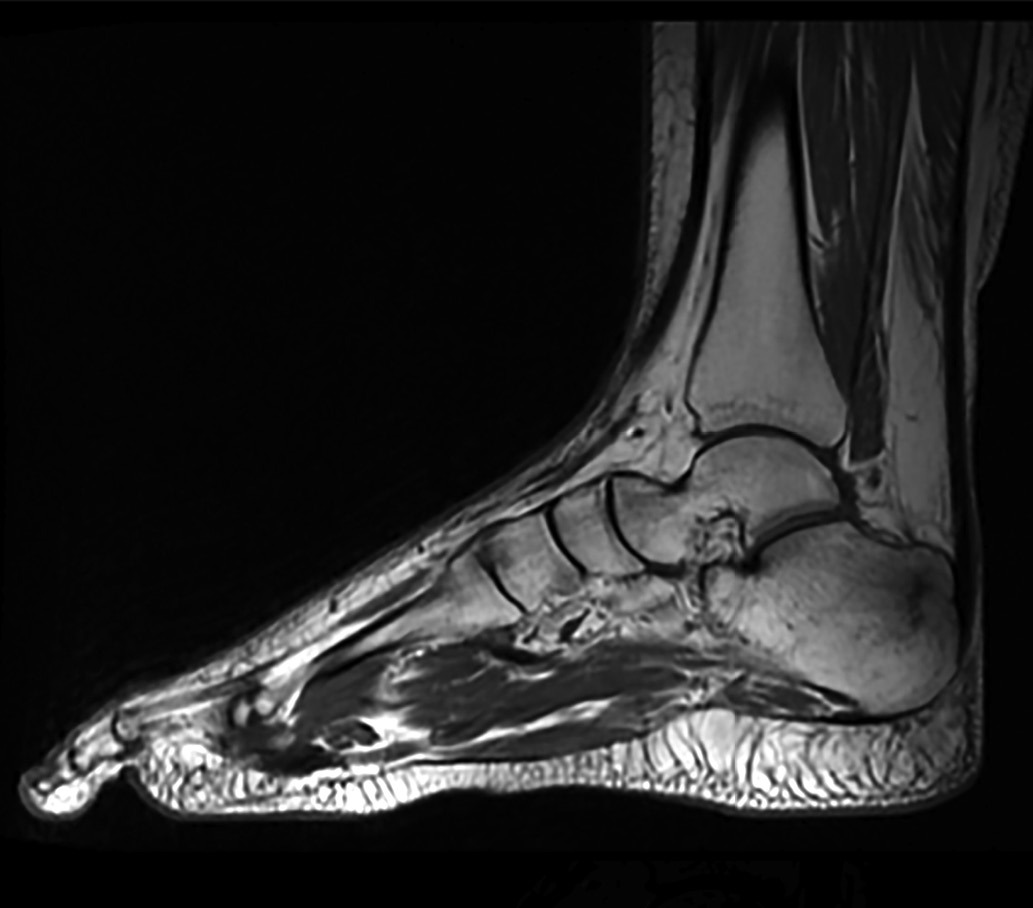

9. Рисунок 9. Магнитно-резонансная томография правого голеностопного сустава в режиме PD. | |